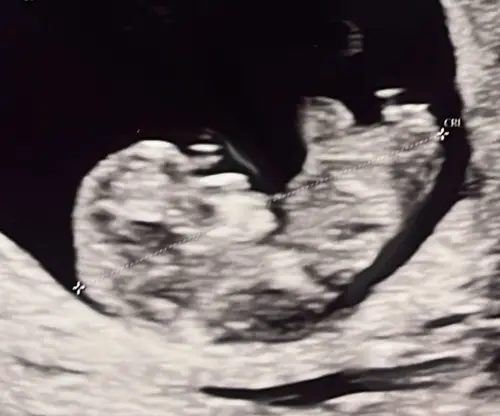

Jongen of meisje? 🩷🩵 13 weken vandaag

Ik denk jongen

Ik denk ook jongen 🩵